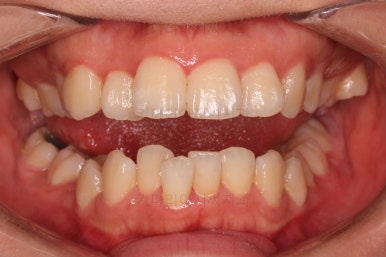

부산무턱교정치과 초진 시 입안의 모습입니다.

전반적으로 치열이 삐뚤고요. 아랫니가 윗니보다 뒤쪽으로 많이 가려져 있죠.

그래서 앞에서 봤을 때 아래 앞니가 거의 보이지 않는 상태인데요.

이런 교합을 "과개교합"이라고 표현합니다.

전반적인 교합, 치열, 과개교합, 튀어나와 보이는 앞니 등을 개선해줘야겠네요.